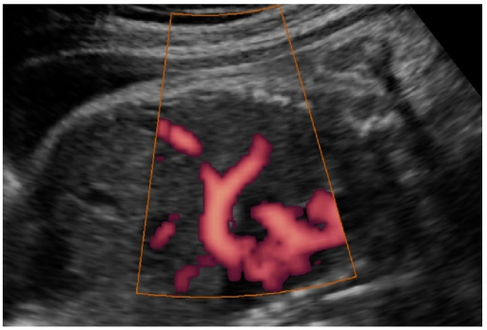

In most cases, postnatal diagnosis is done and up to 2011, only four cases are reported via prenatal diagnosis.[3] Congenital diaphragmatic hernia and intrauterine growth retardation (these two signs put the patients at the risk of afflicting with ring chromosome 15) by fetal ultrasound (Obstetric ultrasonography) at the time period of 16–24 weeks, further investigation and diagnostics (such as karyotyping) must be performed to test the possibility of ring chromosome 15.[citation needed]

Ultrasound finding in a fetus showing liver herniation into the thorax

Congenital diaphragmatic hernia